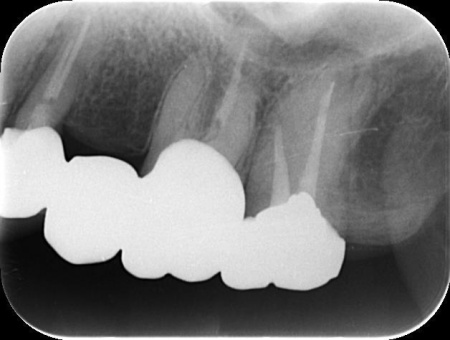

拝見したところ、左上の歯(第2小臼歯)が欠損しており、この部分を補うために、両隣の歯を土台として橋を渡すように連結した被せ物「ブリッジ」が装着されていました。

レントゲン撮影をして詳しく検査した結果、ブリッジを支えている左上の歯(第1小臼歯)は、歯根が割れていることが判明しました。

第1小臼歯に歯根破折を認めました。